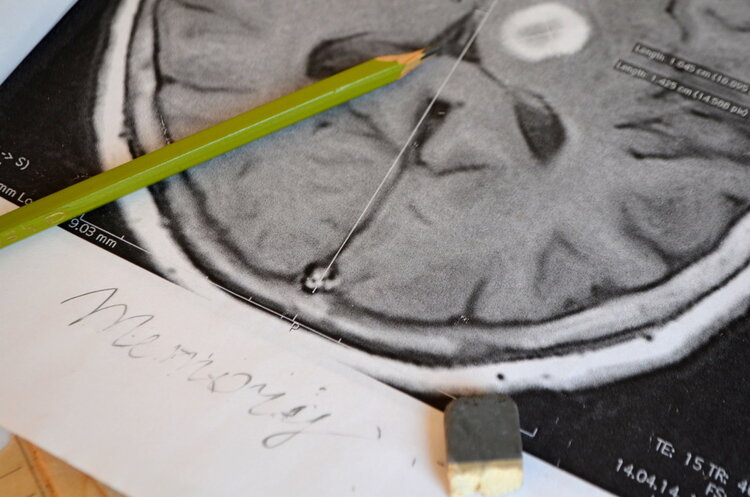

颈动脉斑块与脑梗息息相关 , 斑块一旦脱落 , 造成栓塞的风险就会大大增加 。 那么 , 颈动脉斑块的最终归宿是脑梗吗?

一是斑块的稳定性 , 如果斑块比较稳定 , 脑梗的风险就相对较小 。 即使斑块引起了动脉狭窄 , 但是只要狭窄程度不高于50% , 对大脑正常供血的影响也不大 。

二是看颈动脉是否因为斑块而出现颈动脉狭窄 , 且狭窄程度高于50% 。 在这种情况下 , 发生脑梗的风险性就比较大 。

而且 , 斑块还存在脱落、破裂等可能性 , 会随着血液流动发生移动 , 从而引起血栓 。 血栓脱落的话 , 就可能导致短暂性脑缺血或缺血性脑梗 。